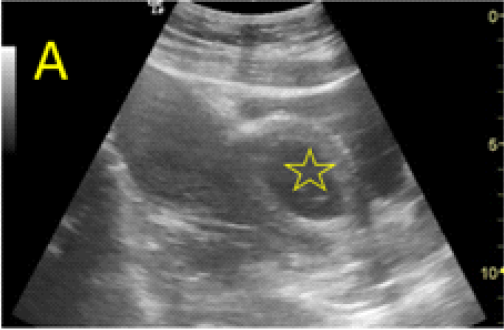

A 22-year-old secundigravida, presented to our Hospital with acute pelvic pain and vaginal bleeding. Her medical history included a 2-year prior caesarean delivery. The patient was in a stable condition and the clinical exam was unremarkable. As the urinary pregnancy test was positive, a transvaginal ultrasound scan was performed to evaluate the pregnancy location and viability. The exam revealed an empty uterine cavity but identified the gestational sac at the level of the caesarean scar with a live embryo (174 beats per minute), measuring 8 weeks and 5 days by crown-rump length. (Figures 1). Because the trophoblastic tissue was noted with an anteriorly location, urinary bladder invasion was suspected based on the ultrasonographic signs: poor identification of the bladder wall, the lack of the sonolucent space and increased vascularization with abnormal pattern (Figure 2). The patient blood tests results were normal, and beta-human chorionic gonadotropin (b-HCG) value was 145.000mUI/ml. After proper counselling and written informed consent the patient opted for a medical conservative treatment with desire to preserve her fertility.

Figure 1. A: the gestational sac is located at the level of the uterine isthmic scar, grey-scale and Power Doppler transvaginal evaluation. B: an embryo with a crown-rump length (CRL) that corresponds to 8 weeks and 1 day is found with normal fetal heart activity (C).

Figure 2. A, B: empty uterine corpus and the presence of the gestational sac at the level of the previous cesarean scar, transabdominal assessment. C, D, E: Same approach, evidence of bulging of the gestational sac into the urinary bladder, with hypervascularity highlighted using Power Doppler evaluation.